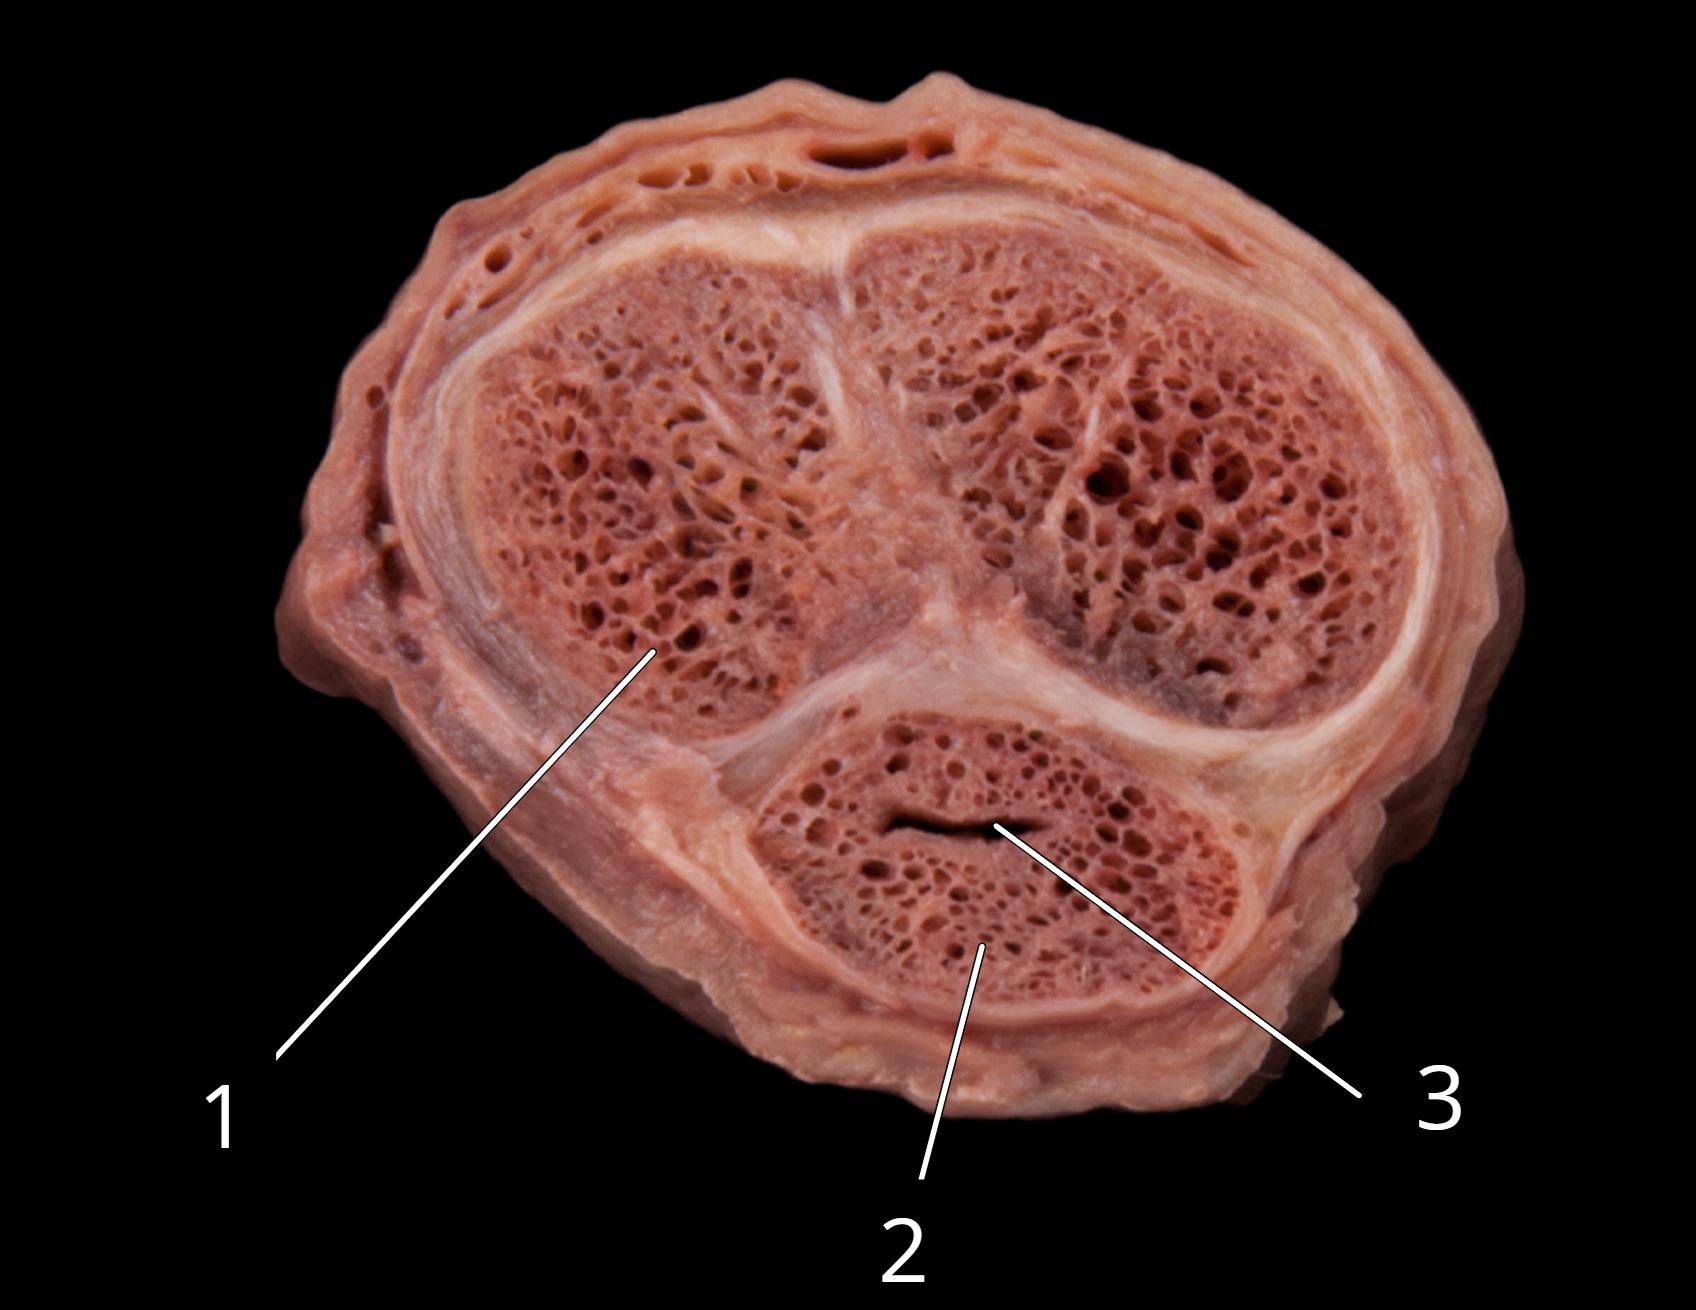

Penis, transverse section

1. Corpora cavernosa

2. Corpus spongiosum

3. Penile urethra